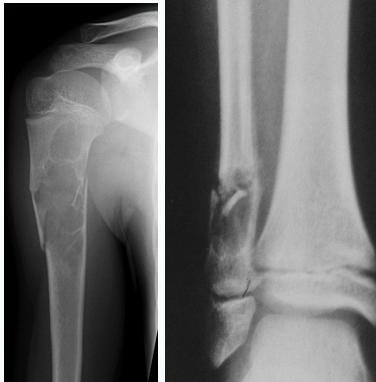

Giant-Cell Tumor

- Unknown origin:

- Giant cells abundant

- Behavior:

- One third benign

- One third locally aggressive

- One third (less) with distant metastasis

- Young adults

- Common sites:

- Around knee

- Proximal humerus

- Distal radius

Radiological Features

- Eccentric lesion:

- Radiolucent

- Soap bubble

- Abuts (adjacent) against the joint

- Thin cortex

- Margins may be clear / unclear:

- Depends on aggressiveness

- Treatment:

- Curettage & bone grafting

- More wide excision in recurrent and aggressive lesions